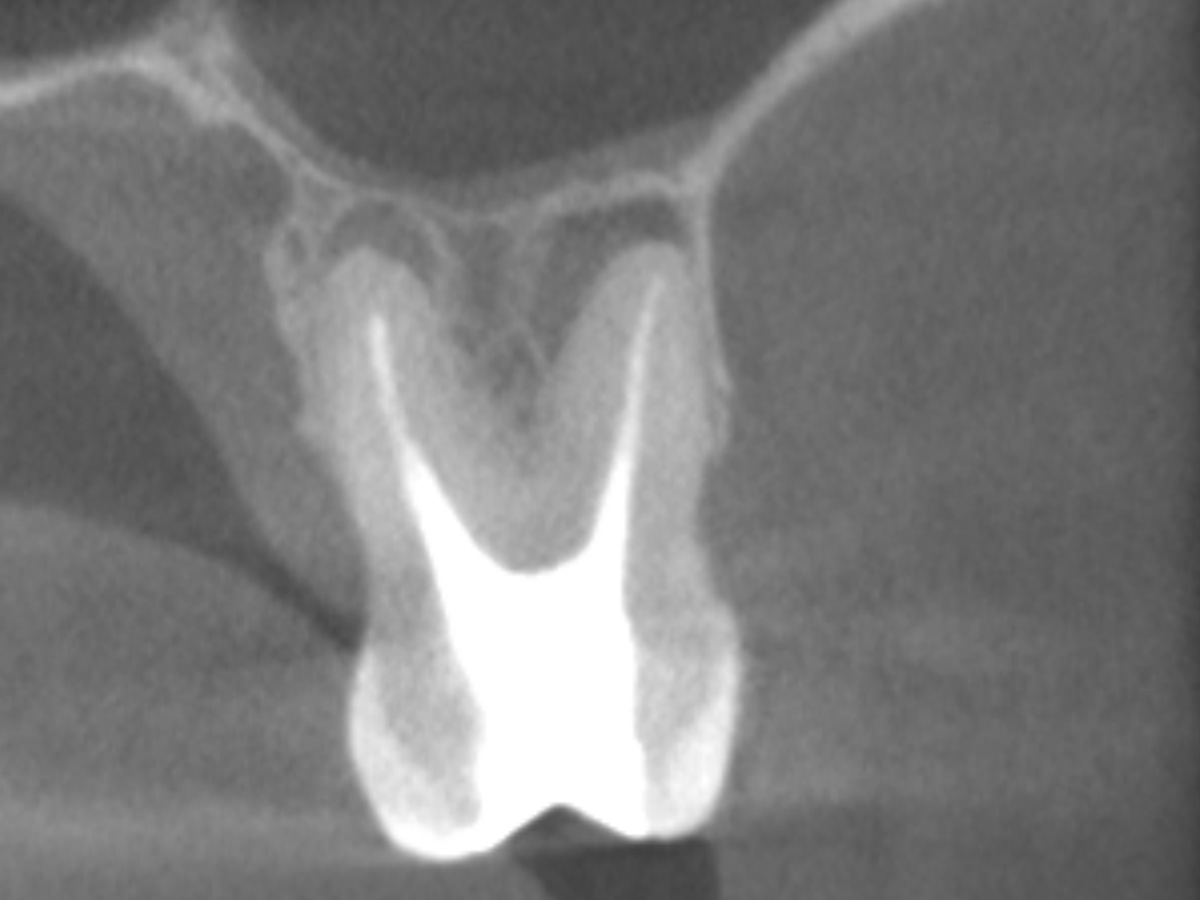

Der Patient stellte sich mit Aufbissschmerzen vor, wobei die klinische und röntgenologische Untersuchung eine symptomatische apikale Parodontitis an einem bereits wurzelkanalbehandelten Zahn 26 ergab. Die DVT-Aufnahme deutete auf einen unbehandelten zusätzlichen Kanal in der mesio-bukkalen Wurzel hin. Die Darstellung und Behandlung des mb2s sowie die Revision der bereits behandelten Kanäle erfolgte mit dem XP-endo® Rise Shaper bei einer hohen Umdrehungszahl von 2.500rpm.

DVT sagittal